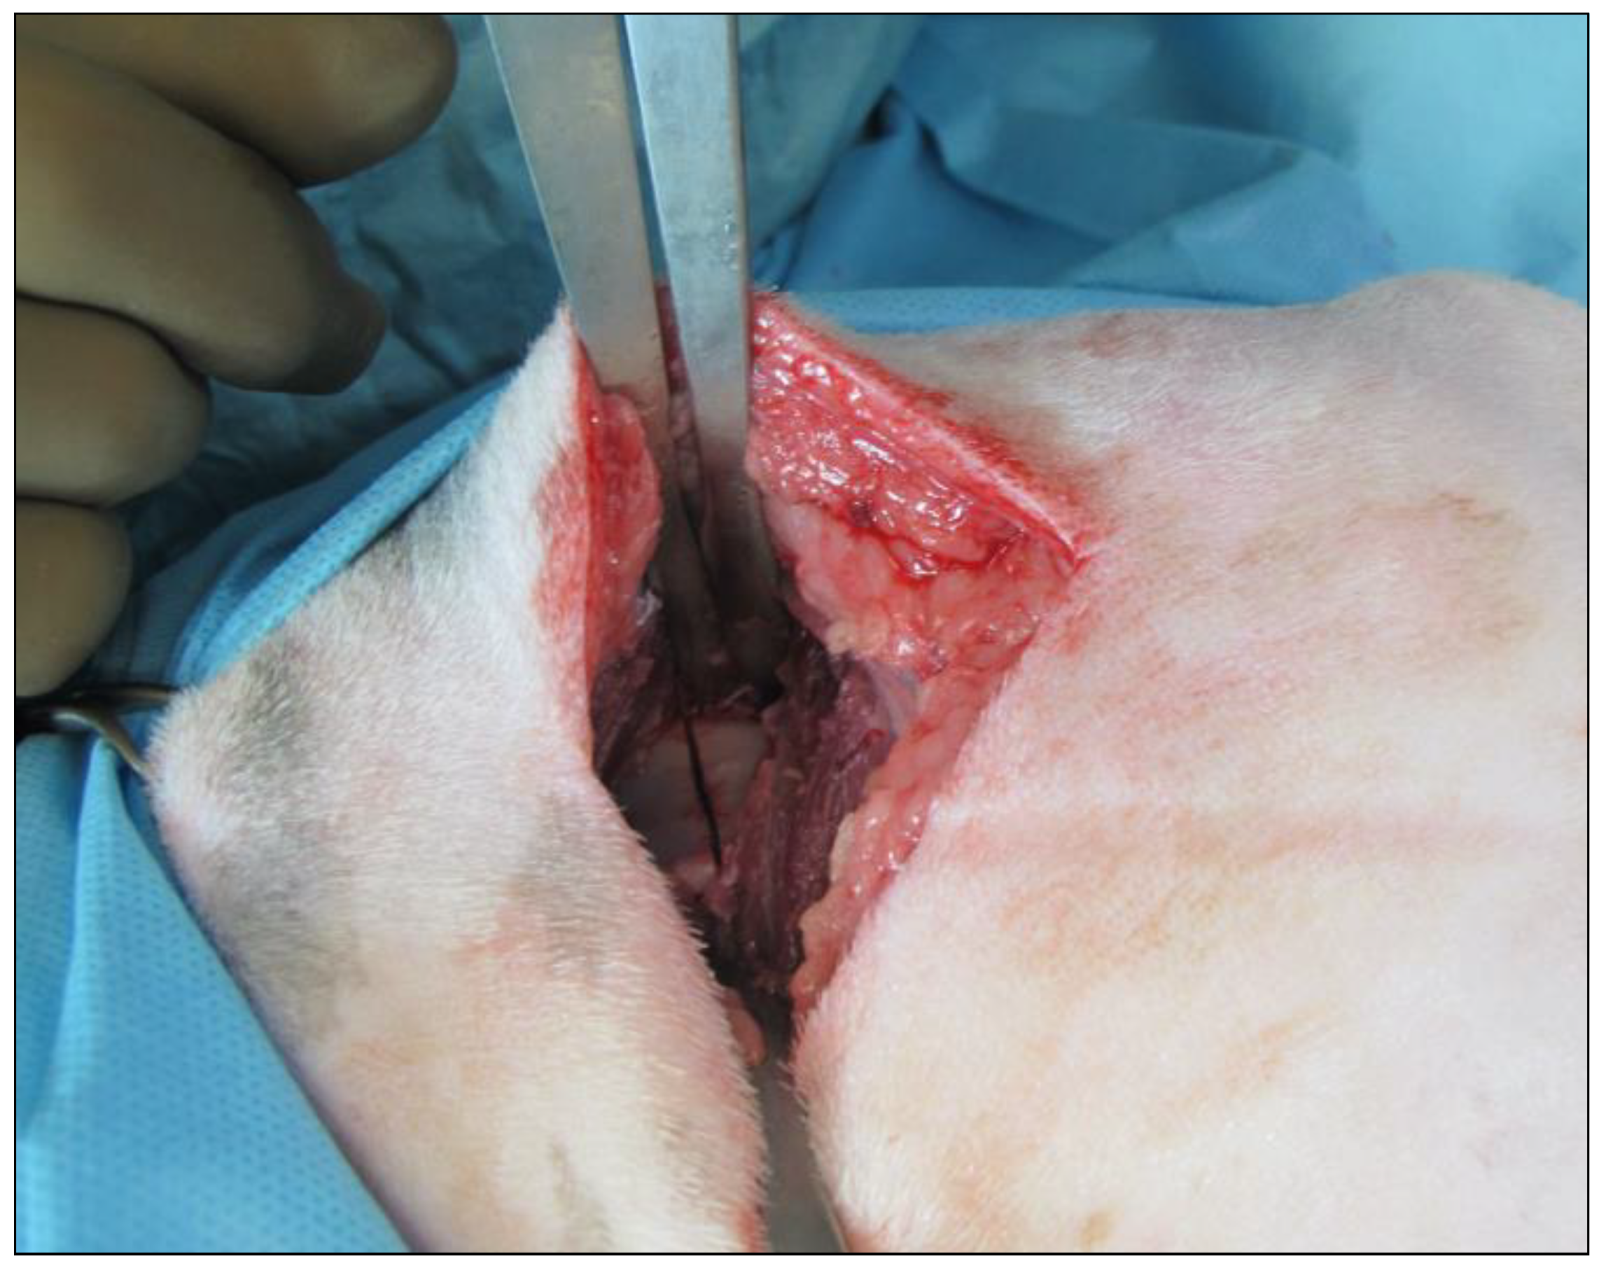

2. Materials and Methods